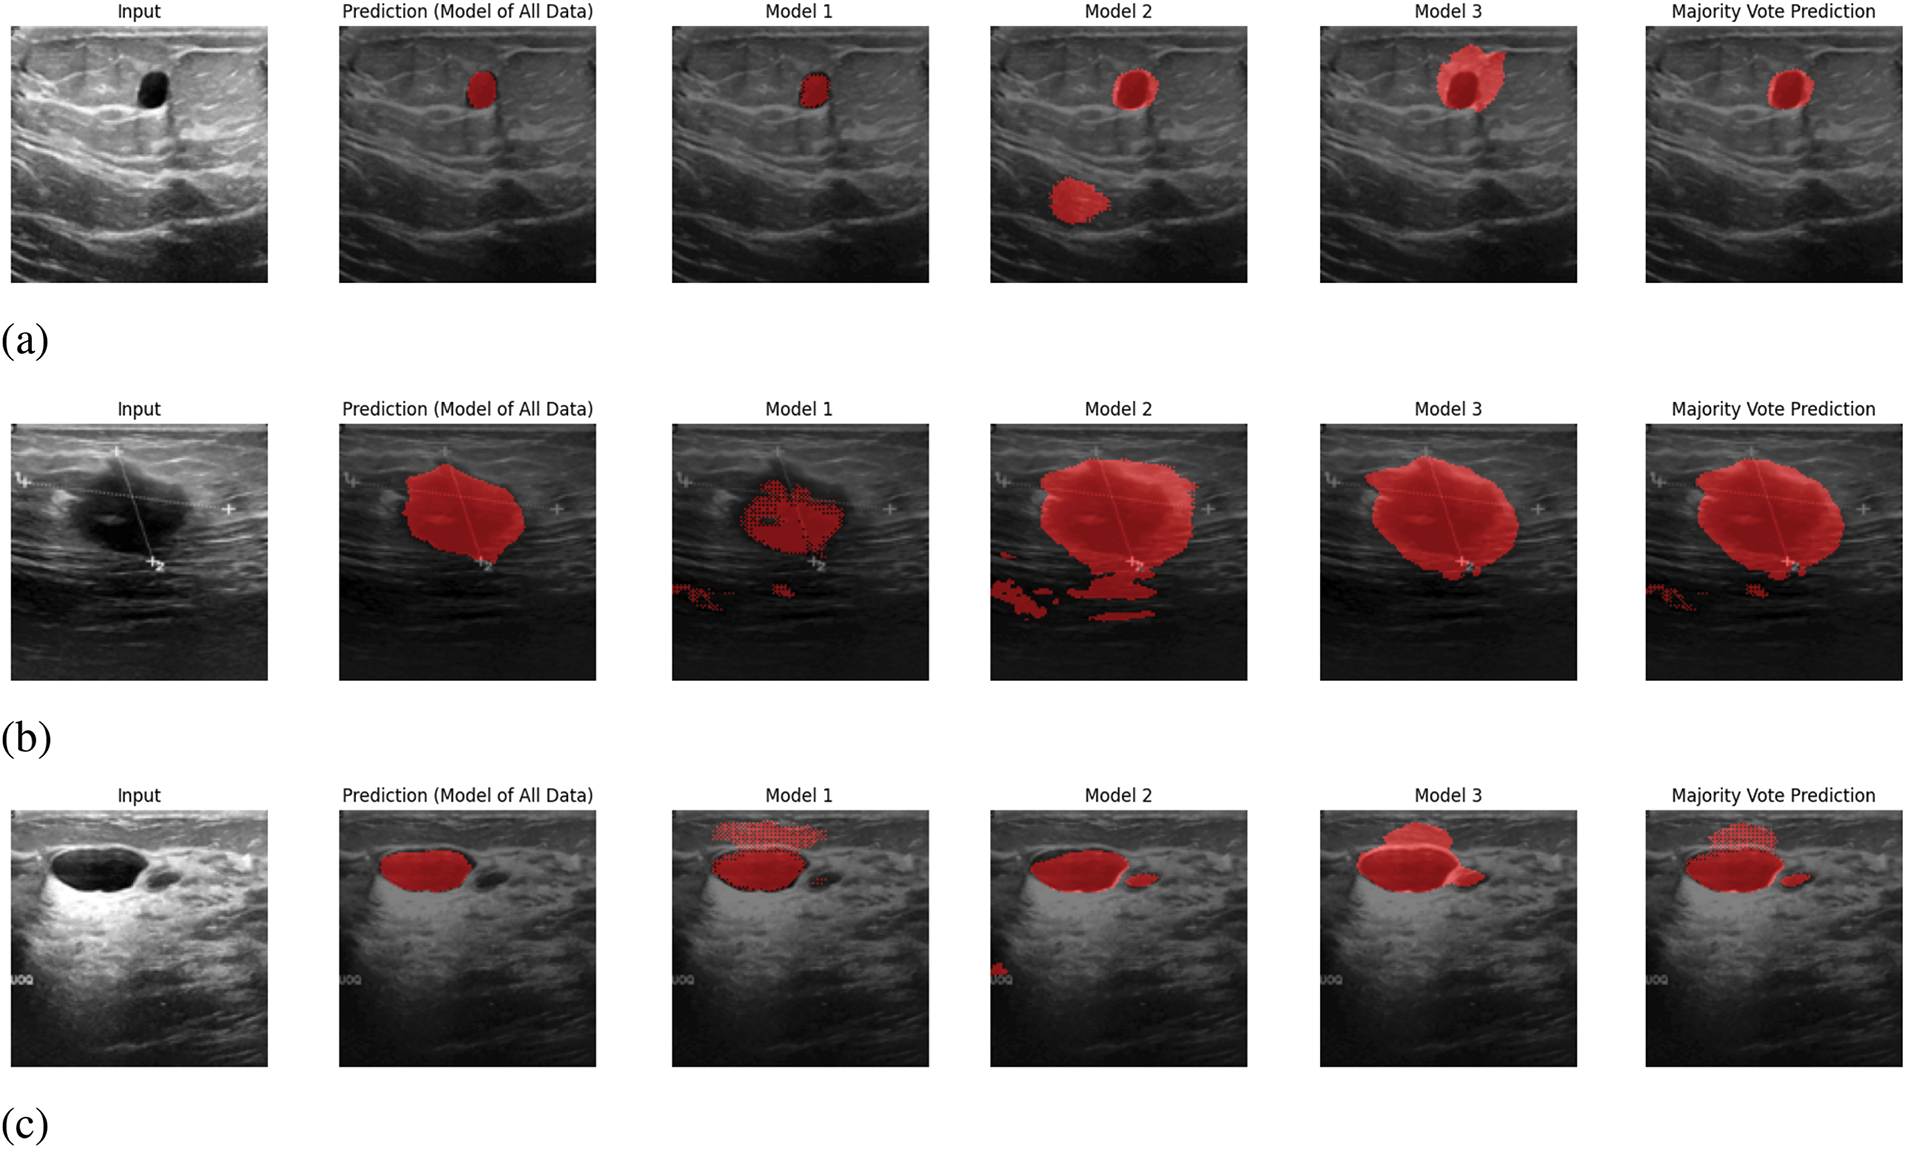

In Fig. 6, sample outputs for 5 inputs are given. In Fig. 6, along with providing the ultimate output, the predicted output from each model is also given. In the proposed system, the output will be predicted from the trained models of each segment, and the ultimate output will be selected based on pixel-wise voting majority. By looking at Fig. 6, it is visible that the ultimate output is almost similar output with the predicted output from the trained model of all data. Therefore, it can be claimed that the proposed prediction system works appropriately.

Figure 6: Sample output predictions: (a) Input 1, (b) Input 2, (c) Input 3, (d) Input 4, (e) Input 5